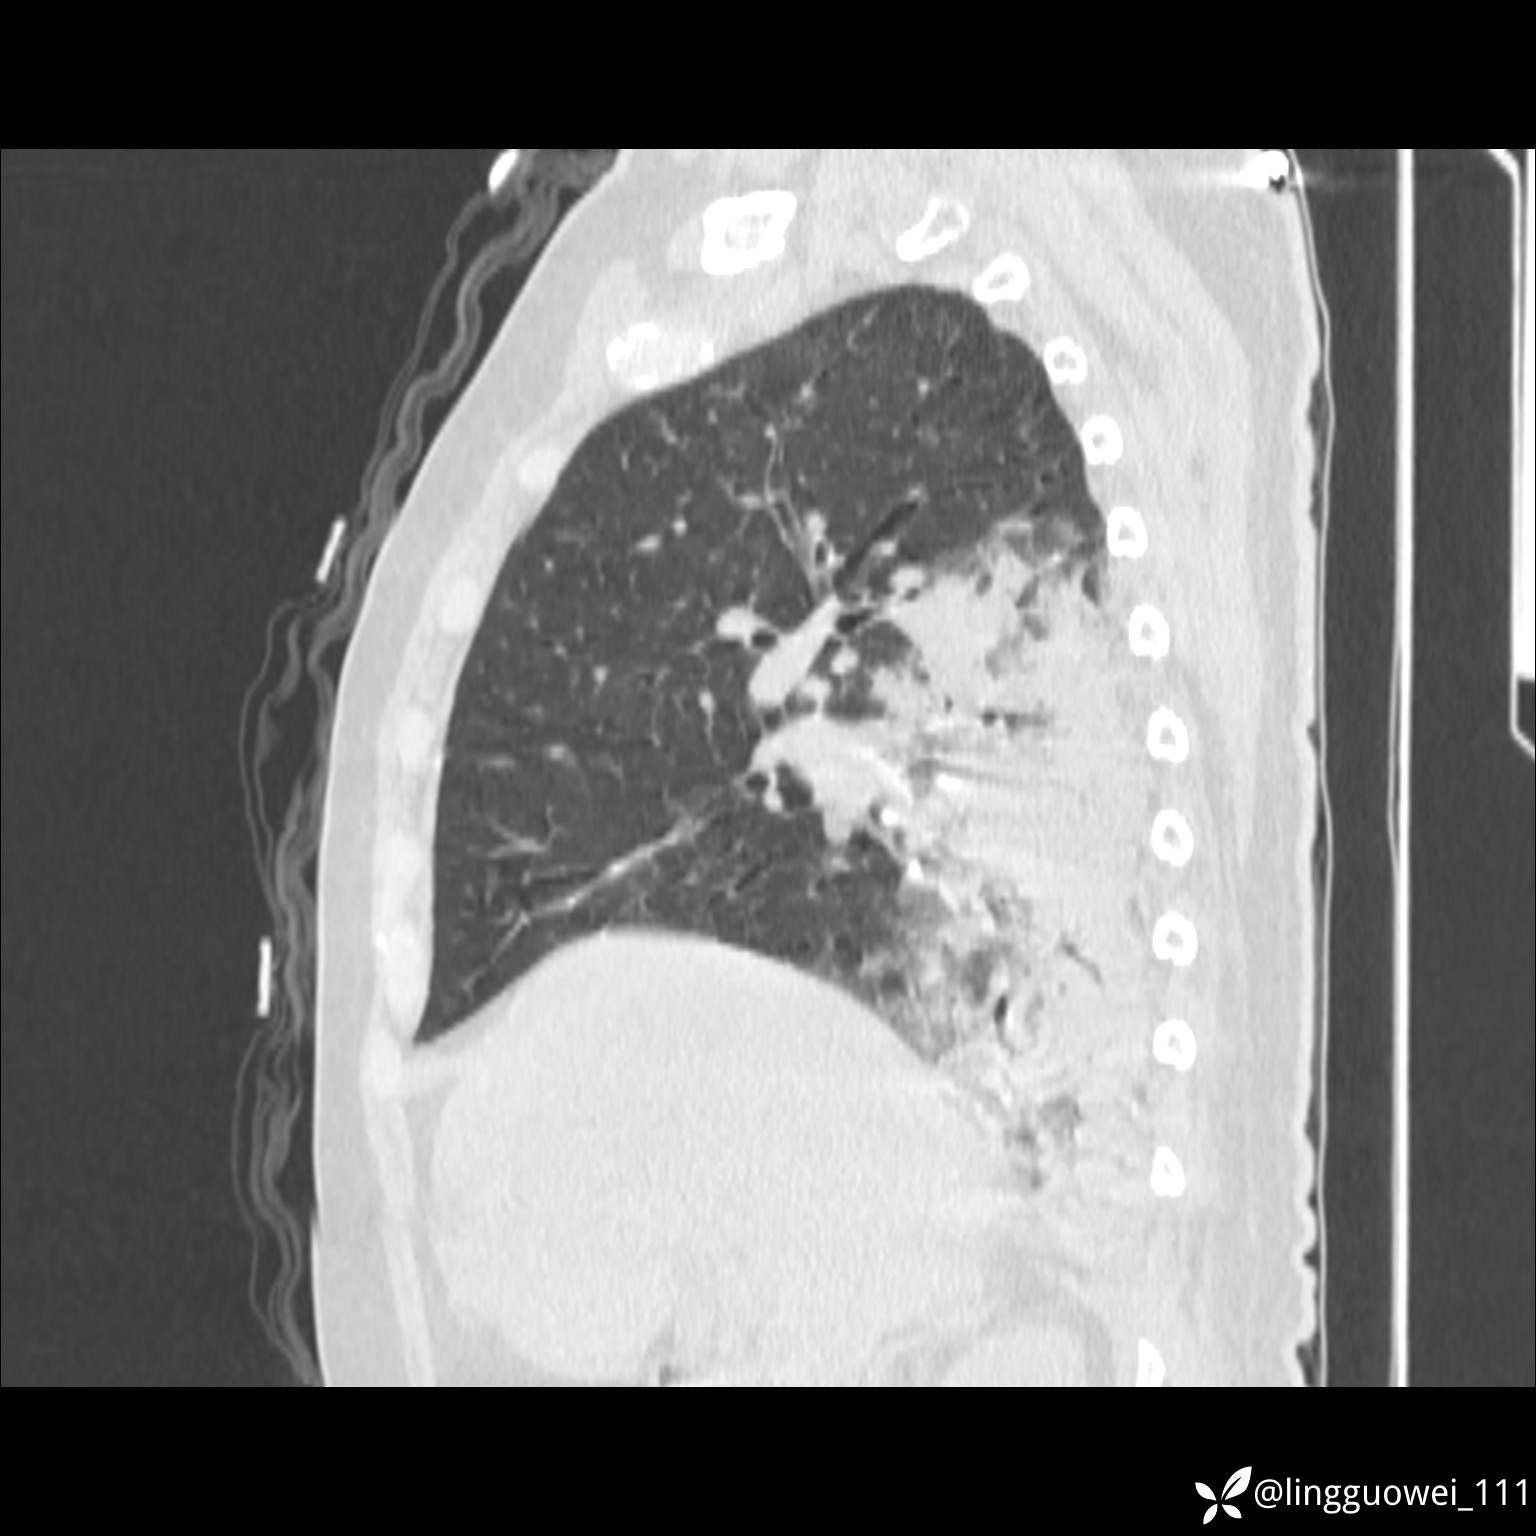

20小时后,行胸部增强检查,病灶范围较前增大